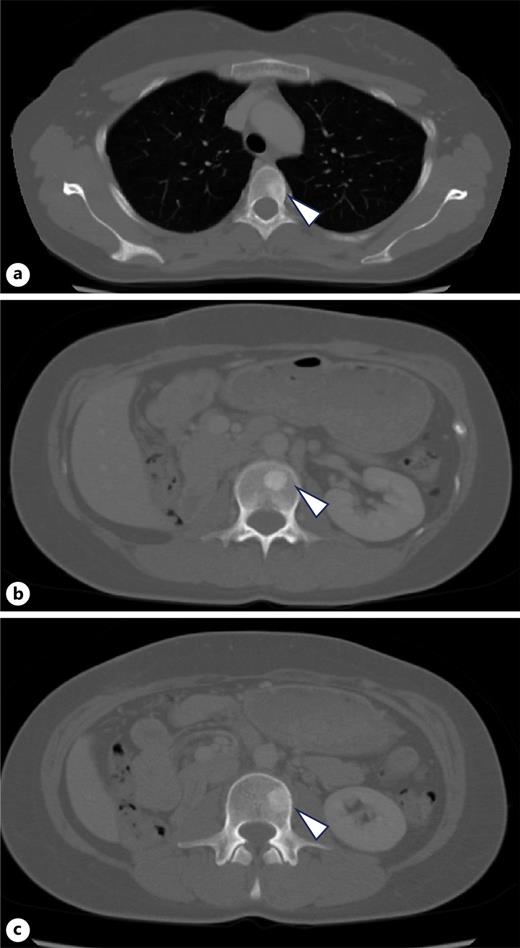

A 34-year-old woman presented with fever and right flank pain. Contrast-enhanced computed tomography (CT) revealed a 116 × 83 mm poorly enhanced solid mass replacing the right kidney, suspicious for RCC and tumor thrombus in the inferior vena cava below the hepatic vein inflow without apparent lymph node or distant metastases (shown in Fig. 1). Brain magnetic resonance imaging (MRI) showed no evidence of brain metastases, and bone scintigraphy revealed no abnormal uptake. The patient’s medical history included depression, and family history was notable for epilepsy in her brother and daughter. Therefore, the patient was diagnosed with non-clear cell RCC at the clinical stage cT3bN0M0. Concurrently, uterine leiomyomas were observed, along with a family history, raising suspicion for HLRCC. Open radical nephrectomy and inferior vena cava tumor thrombectomy were performed. Pathological findings revealed atypical tumor cells with irregular glandular structures and large nucleoli resembling nuclear inclusions. Immunohistochemical analysis showed loss of FH protein in the tumor cells, confirming the diagnosis of FH-deficient RCC, pT3bN0M0, stage III, WHO/ISUP grade 3 (shown in Fig. 2). PD-L1 expression and CD4/CD8-positive lymphocyte infiltration were observed, although most infiltrating lymphocytes were stromal with minimal intratumoral infiltration. Four weeks postoperatively, CT showed no recurrence. Adjuvant immunotherapy with pembrolizumab was initiated owing to the pT3b stage. Genetic counseling was performed with informed consent. Gene sequencing using a hybrid capture method identified a missense variant of FH c.698G>A (p.Arg233His) [NM_000143.4]. According to the ClinVar database (variation ID: 16236), the clinical significance of FH c.698G>A is pathogenic. Combined with her phenotype, we confirm the diagnosis of HLRCC. At week 9 of pembrolizumab therapy, CT revealed bone metastases at Th4, L2, and L3 (shown in Fig. 3). After discussing the available treatment options along with their respective benefits and drawbacks, the patient chose to pursue the most intensive therapy despite potential side effects. These oligometastases were treated with stereotactic body radiotherapy (SBRT) (24 Gy in two fractions). Therefore, systemic therapy with NIVO (240 mg) and cabozantinib (40 mg) was initiated. The patient remained stable disease for 16 months since the recurrence. Genomic testing using the FoundationOne CDx® panel identified the known FH mutation and genetic abnormalities in PIK3R1 and TP53; however, no additional actionable mutations were detected. Mutations in BRCA1/2 have been identified; however, these have been classified as variants of uncertain significance. After undergoing multidisciplinary genetic counseling, the patient consented to genetic testing of her 9-year-old daughter, which revealed the same FH gene mutation. Consequently, annual MRI screening of pediatric patients was initiated.

Multiple bone metastases that had not been detected on CT before the initiation of adjuvant therapy. a Th4. b L2. c L3.